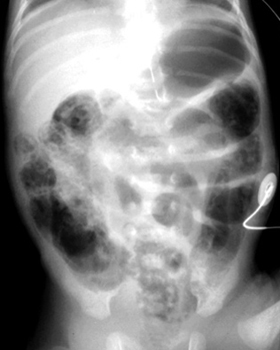

A

definitive radiographic finding is pneumatosis, gas in the bowel wall.

There is a "frothy" or "soap-bubble" bowel gas pattern. Linear or cresent shaped gas collections in the bowel wall may also be seen.

Another sign is unchanged bowel gas pattern over several films indicating

an ileus. More worrisome signs include gas in portal venous system and ascites.

| Multiple dilated loops of bowel with pneumatosis. | Extensive pneumatosis throughout the abdomen. |